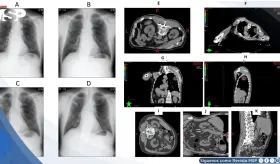

A pesar de mostrar un aumento radiológico del tumor durante la quimioinmunoterapia neoadyuvante, la cirugía reveló una respuesta patológica completa, subrayando la complejidad de la pseudoprogresión.

La paciente desarrolló simultáneamente un carcinoma mamario triple negativo de rápido crecimiento y un adenocarcinoma rectal invasivo, ambos confirmados como tumores primarios independientes.